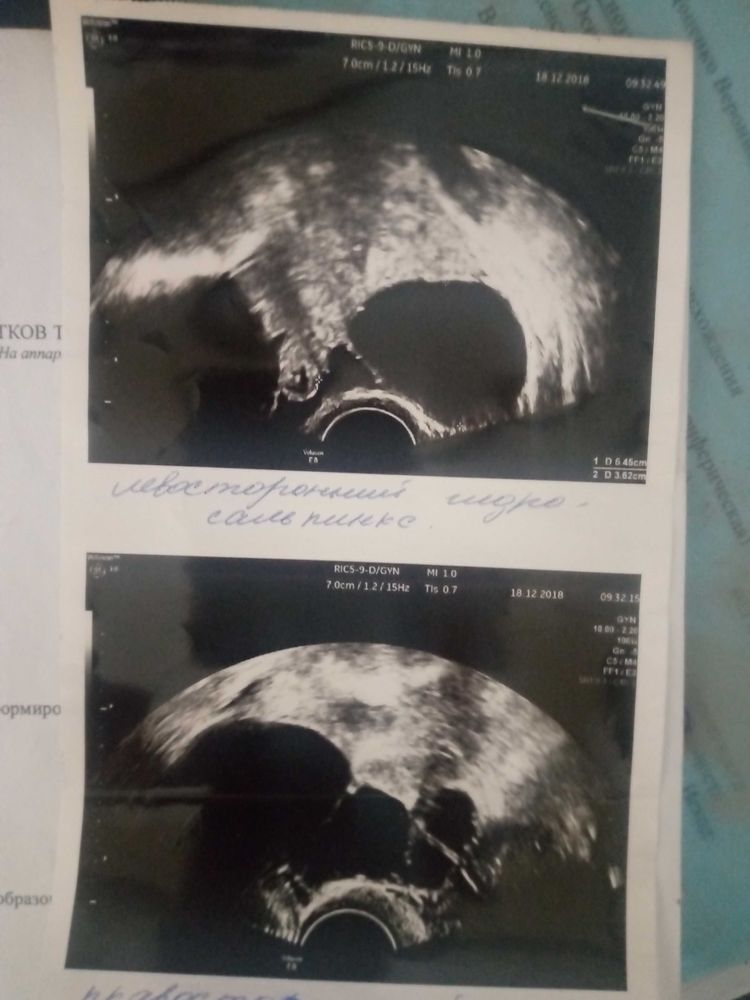

Так выглядели мои гидросы на УЗИ, но на плановую лапару не успела, ночью обе трубы пошли на разрыв. Забрали по скорой с пельвеоперитонитом, удалили, в гистологии указали, что это не гидро,а сактосальпингс,т.е гнойный.